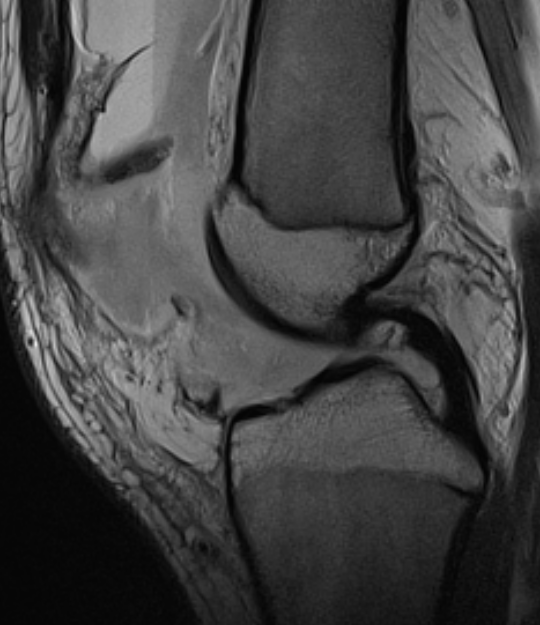

Large osteochondral fracture medial facet patella

Open reduction and internal fixation

Approach

Patella - medial parapatellar approach with knee extended

Lateral femoral condyle - lateral parapatellar approach with knee flexed to 90

Fixation

Headless compression screws